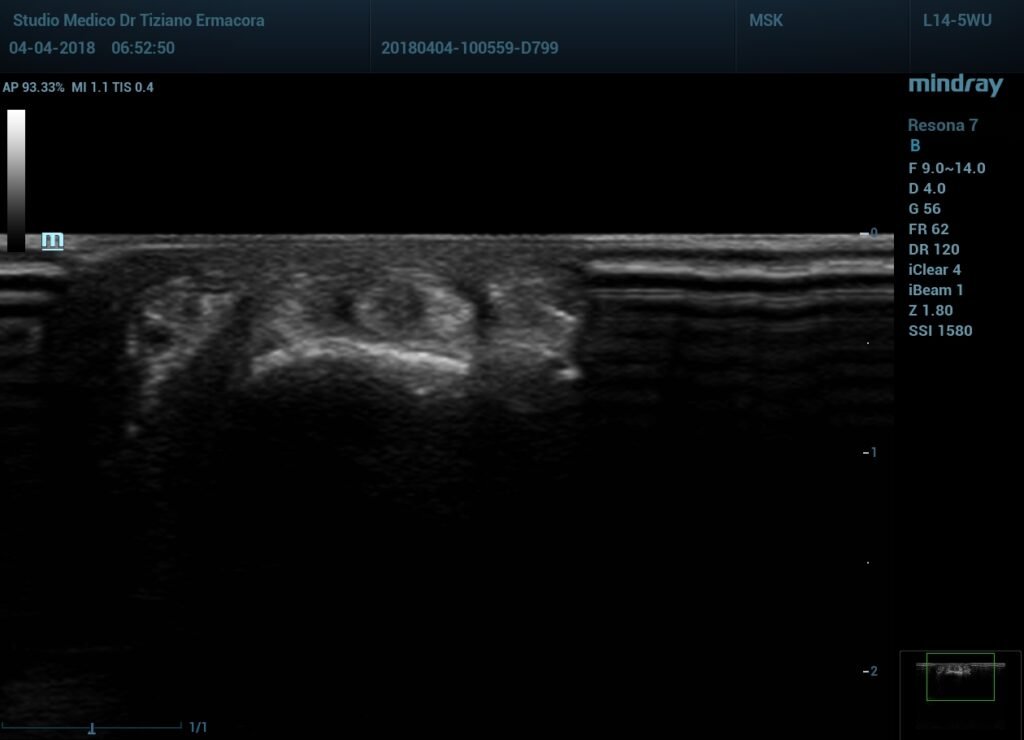

Tendinite flessore del pollice

Tendinite flessore del pollice,infiltrazione ecoguidata